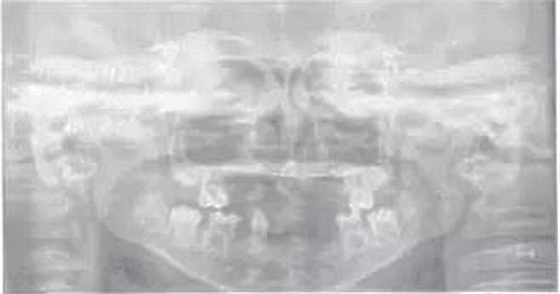

頜面斷層檢查:運用數(shù)字放射影像技術評估患者缺牙區(qū)牙槽嵴和下頜骨解剖狀況,追問病史,患兒家長否認近親結(jié)婚史及家族史。診斷為:(1)小兒軟骨外胚層發(fā)育不全綜合征;(2)牙列缺損。就診后,行全面口腔檢查,取模,制作研究模型。經(jīng)與患者協(xié)商溝通,采用覆蓋義齒修復。

圖1患兒曲面斷層片